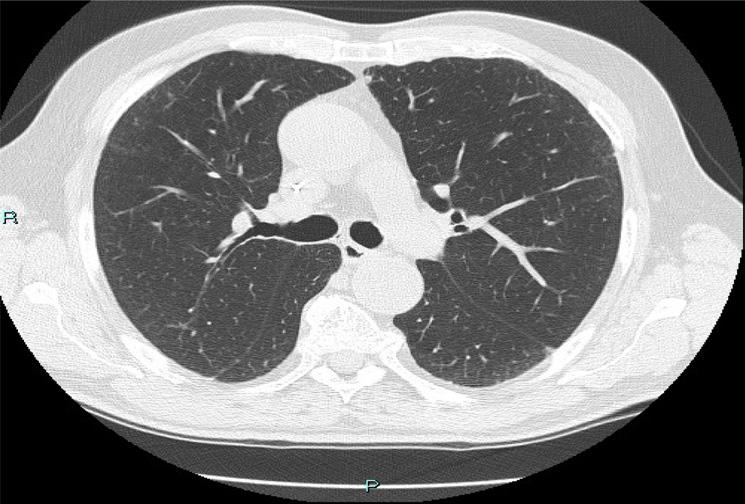

Tuttavia, nonostante la buona risposta iniziale, la TC total body con mezzo di contrasto del 28/12/2023 (figura 1) evidenzia progressione epatica ed encefalica con un quadro radiologico che mostra sovvertimento encefalico diffuso caratterizzato da numerose lesioni secondarie (almeno 10) a netta impregnazione contrastografica a sede sia cerebrale che cerebellare, prevalentemente subcentimetriche, la maggiore di 13 mm in nucleo-capsulare sx con nucleo necrotico e modesto alone edemigeno perilesionale.

La paziente, asintomatica sul piano neurologico e con marcatori tumorali negativi, viene sottoposta previo consulto multidisciplinare, a radioterapia panencefalica con risparmio dell’ippocampo con tecnica IMRT (30 Gy in 10 frazioni) e candidata poi a trattamento di II linea con T-DXd (5,4 mg/kg) q21, supportati dai dati di efficacia riportati dal DESTINY-Breast03, dalle analisi di sottogruppo degli studi DESTINY-Breast01, -02, -03 e dagli incoraggianti risultati preliminari degli studi DEBBRAH e TUXEDO-1.

La rivalutazione strumentale effettuata dopo 4 cicli di trattamento (figura 2) ha mostrato risposta intracranica completa ed epatica parziale. Lo studio della regione mammaria e ascellare con ecografia mammaria e mammografia ha mostrato assenza di lesioni infiltrative con presenza in sede retroareolare sx di un cluster di microcalcificazioni in assenza di linfoadenopatie ascellari. Lo studio tomografico con finestra per osso ha confermato la sovrapponibilità delle lesioni ossee rispetto alla precedente TC, in assenza di fratture patologiche. La paziente tuttora non ha mai manifestato eventi scheletrici secondari né riferisce dolore.